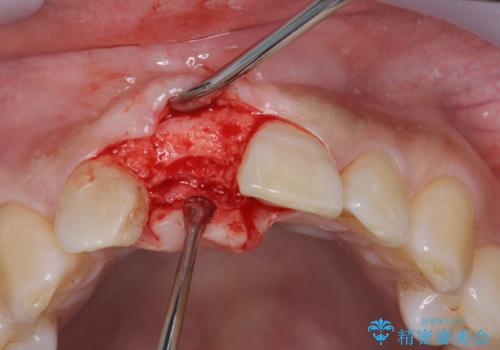

審美的・機能的に良好な位置に埋入するには、骨量が十分ではなかったため骨の造成を併用したインプラント埋入外科手術を行います。

前歯のインプラントを審美的に仕上げるには、インプラント周囲に十分な骨の量と厚みのある歯肉、そして埋入位置の精密な位置付けが重要です。